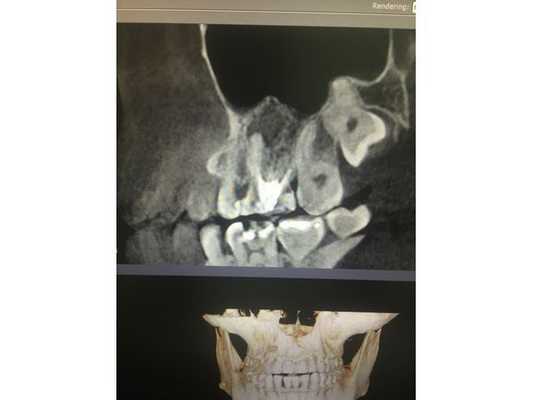

По данным компьютерной томограммы, в зубе три канала, тень пломбировочного материала определяется на всём протяжении каналов в виде непрерывной линейной структуры, рентгенологически верхушки корней зуба обтурированы, т. е. закрыты.

Обнаружен дополнительный канал со стороны щеки, содержимое канала не просматривается. В области нёбного канала видна тень металлической плотности, по конфигурации она соответствует анкерному штифту.

В области верхушек корней визуально определяется деструкция (разрушение) кости без чётких контуров. Плотность участка разрушения снижена, характерный костный рисунок частично сохранён. Область разрушения частично затрагивает альвеолярную бухту гайморовой пазухи. Кортикальная пластинка, отделяющая гайморову пазуху от зубов, в проекции деструкции прослеживается фрагментарно.

Через два года после лечения сделали контрольную компьютерную томографию. Кость вокруг корня зуба полностью восстановилась. Обострений, боли и дискомфорта после лечения пациент не отмечал.